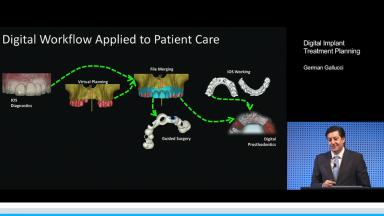

This lecture describes the evolution of digital technologies and related workflows in restorative and implant dentistry. The basis of the lecture is the clear advantage of treating the patient virtually before starting any interventions. The diagnosis and planning portions of a digital workflow are outlined in a step-by-step manner, beginning with the merging of a DICOM file from a cone beam CT scan with an STL file from an intraoral or extraoral scan. Based on the merged file, three types of prosthodontic planning are presented: the functional, digital, and dual scan methods. The lecture concludes with the presentation of a virtually planned case from start to finish.